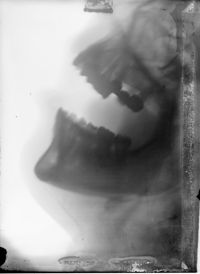

Image[Radiographie. Maxillaires supérieur et inférieur de profil, bouche ouverte.]